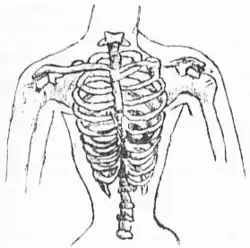

В середине XIX столетия корсеты стали предметом резкой критики со стороны медиков. Врачи настаивали на негативном влиянии корсета на женский организм — медицинская критика фактически вытеснила отрицательную оценку этого вида одежды моралистами[2].

Ношение корсета представляет собой один из вреднейших и опаснейших для здоровья обычаев. Стягивание грудной клетки, особенно нижней, наиболее податливой её области, влечёт за собой нарушение правильной деятельности органов грудной и брюшной полостей. Вследствие сжатия нижних долей лёгких кровь недостаточно окисляется и в результате получается малокровие и неправильная деятельность сердца. Вместе с тем сдавливаются и смещаются печень, желудок и кишечный канал, причём первая нередко претерпевает местами рубцовое перерождение, а другие органы, оттеснённые вниз, давят на органы тазовой полости и на крупные брюшные сосуды. Усиленные движения (танцы, езда на велосипеде) при туго стянутом корсете нередко бывали причиной внезапной смерти. В громадном большинстве случаев тугое стягивание корсета служит причиной развития самых разнообразных женских страданий, а, сдавливая соски и сами грудные железы, лишали женщин возможности кормить своих детей грудью.Энциклопедический словарь Брокгауза и Ефрона / под ред. проф. И. Е. Андреевского. Т. 16. — СПб., 1895.

Корсеты начинали носить в возрасте 4—5 лет, что приводило к систематическим искажениям костной ткани: ребра и внутренние органы развивались с нарушениями и приобретали деформации. В 1903 году парижский врач Жозефина Гош-Саро предложила разделить корсет на две составляющих: верхнюю — для поддержки груди, и нижнюю — пояс для чулок. Это деление было положено в основу бельевой схемы всего XX века и, фактически, сохраняется в женской нижней одежде до сих пор. Несмотря на критику, корсет оставался центральным элементом одежды на протяжении нескольких столетий.